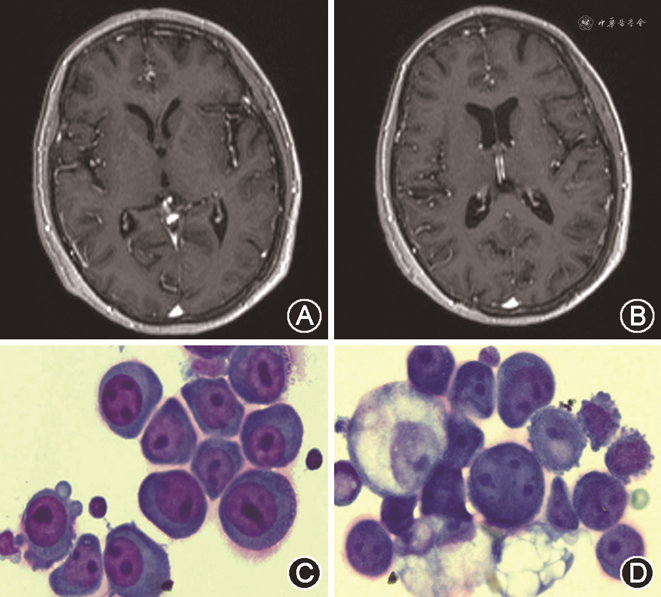

入院后神经系统体检:意识清楚,语言流利,精神差,高级智能检查正常,脑神经检查无异常,四肢肌力肌张力正常,双侧病理征阴性,颈稍抵抗感,颌胸2横指,余神经系统体检未见明显异常。心肺腹无异常。神经系统定位诊断:头痛定位于颅内痛敏结构,颈抵抗定位于脑膜;定性诊断:炎症性疾病?脑膜转移?进一步完善相关辅助检查:血常规:白细胞计数2.05×109/L,红细胞计数2.94×1012/L,血红蛋白103 g/L,淋巴细胞计数0.43×109/L,中性粒细胞计数1.38×109/L。尿便常规正常。血生化检查:血脂:总胆固醇5.76 mmol/L,高密度脂蛋白胆固醇0.85 mmol/L,低密度脂蛋白胆固醇4.00 mmol/L,极低密度脂蛋白胆固醇0.91 mmol/L;肝肾功能、血同型半胱氨酸、空腹血糖、糖化血红蛋白均正常。红细胞沉降率56 mm/h;降钙素原0.32 ng/ml;C-反应蛋白正常。贫血三项:维生素B12 1 129.0 pg/ml;铁蛋白318.60 ng/ml,余正常。D-二聚体245.0 ng/ml。甲状腺功能、凝血功能未见明显异常。乙型肝炎五项(乙型肝炎表面抗原、乙型肝炎表面抗体、乙型肝炎e抗原、乙型肝炎e抗体及乙型肝炎核心抗体)、丙型肝炎、梅毒、人类免疫缺陷病毒抗体未见异常。影像学检查:头颅MRI+MRA+增强(2021年11月11日):双侧基底节区腔隙性脑梗死;双侧额、顶叶皮质下变性灶;脑萎缩;左侧上颌窦炎症;颅脑MRA未见异常;增强未见明显强化病灶(图1A、B)。脑脊液检查:在患者知情同意下行腰椎穿刺术,颅内压280 mmH2O(1 mmH2O=0.009 8 kPa),脑脊液常规、生化:白细胞数60×106/L,蛋白0.61 g/L,葡萄糖1.5 mmol/L,氯化物127 mmol/L,乳酸4.7 mmol/L。脑脊液细胞学检查(玻片离心沉淀法):镜下可见成簇体积增大,核大,核形态多变,核染色粗,可见核仁,核质比例失调,胞质嗜碱性,细胞形态及特点考虑为肿瘤细胞(图1C、D)。